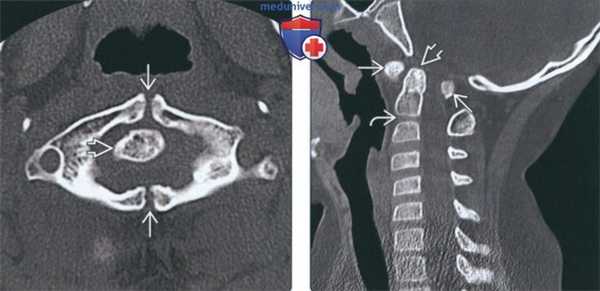

(Слева) На аксиальной КТ в костном окне определяется уменьшение передне-заднего размера на фоне его гипоплазии наряду с расщеплением и срединными дефектами передней и задней дуги. Определяется утолщение и дисплазия зубовидного отростка.

(Справа) На сагиттальной КТ в костном окне у пациента с расщеплением С1 определяется легкая дисплазия зубовидного отростка и патологическая гипоплазия С1 с тяжелым стенозом позвоночного канала. Обратите внимание на сопутствующее нарушение сегментации С2/С3.

(Слева) На аксиальной КТ в костном окне определяются большие срединные костные дефекты передней и задней дуги С1. Широкие щели свидетельствуют о нестабильности.

(Справа) На корональной КТ в костном окне на фоне врожденного сколиоза определяются распространенные нарушения сегментации шейных и грудных позвонков. Боковые массы С1 независимо смещены кнаружи в противоположных направлениях (расщепление атланта). Такая конфигурация крайне нестабильна и требуется спондилодез.

(Слева) Аксиальный КТ-срез: уменьшенное в передне-заднем направлении гипопластичное кольцо С1, имеющее характерную конфигурацию «расщепленного кольца», характеризующуюся наличием дефектов передней и задней дуги. Зубовидный отросток утолщен и также диспластичен.

(Справа) На сагиттальном КТ-срезе пациента с расщеплением кольца С1 видны умеренно диспластичный зубовидный отросток и признаки гипоплазии кольца С1, являющиеся причиной тяжелого стеноза спинномозгового канала. Обратите внимание на сочетанное нарушение сегментации С2/3. (Слева) На аксиальном КТ-срезе определяется широкий срединный костный дефект передней и задней дуг атланта. Такой широкий дефект позволяет предположить наличие нестабильности.

(Справа) На фронтальном КТ-срезе представлен случай врожденной сколиотической деформации и распространенной аномалии сегментации шейно-грудного отдела позвоночника. Боковые массы С1 независимо друг от друга смещены в противоположных направлениях, что обусловлено расщеплением атланта у данного пациента. Это очень нестабильный тип аномалии, требующий хирургической стабилизации.